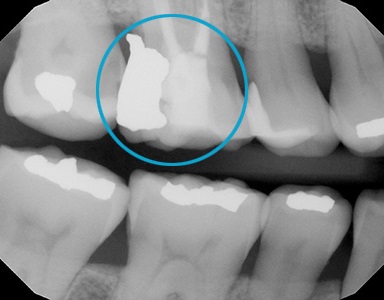

Trauma Case.

The patient had an accident and broke her lower front tooth. We put the fragment back and it looks just as nothing happened.

Tooth Fragment.

For a regular dentist, this may take 2 -3 appointments to fix, more tooth structure loss due to crowning, and might cost thousands of dollars. However, with Dr. Tao's expertise, such problems can be easily fixed with accuracy and high-quality in as little as one day.